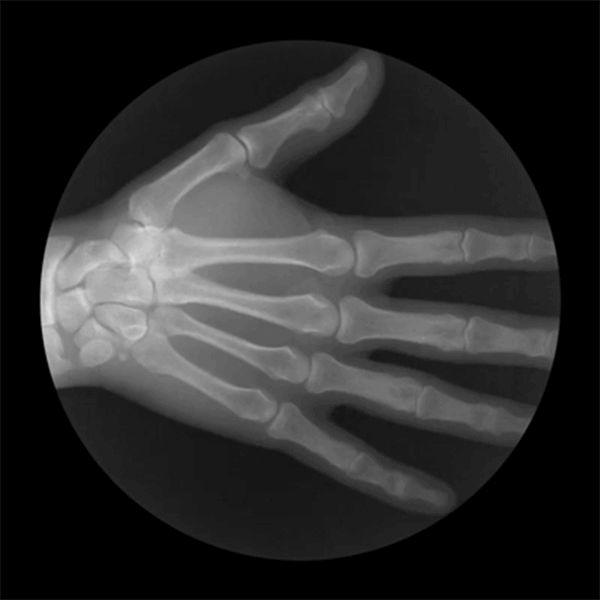

Estas son las radiografías del esqueleto humano sonde se ve cómo pacientes flexionan los brazos, las rodillas y los tobillos. Ver gifs…